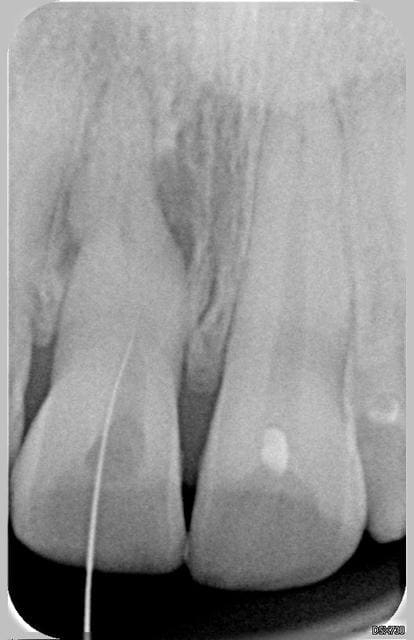

et aujourd'hui, je continue à progresser en direction du "trait de fracture", mais on voit à la dernière radio que j'y suis, mais impossible de desccendre plus, ni de trouver l'entrée de la racine.

Je n'ai jusqu'a présent suivi que le trajet de la dentine tertiaire, je n'ai pas trouvé de lumière canalaire.

J'ai remis un EDTA, serait-ce suffisant pour le prochain rendez vous dans 15 jours ?

Dois-je de suite l'adresser à un exclusif ?

faut-il extraire et poser un implant ?

toutes les remarques et conseils sont les bienvenus

30.11 - Eugenol